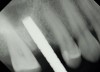

Due to the need for medical treatment for shoulder and neck issues, the patient was delayed in returning to the office for subsequent evaluation. At the 7-month postoperative appointment, the socket was assessed and a panoramic radiograph was taken to evaluate the bone at the planned implant site (Figure 1). The socket was filled with bone that was indistinguishable from the patient's native bone adjacent to the site. Insufficient height to place an implant was noted, which would require a crestal sinus lift prior to implant placement. A cone-beam computed tomography (CBCT) scan was ordered for planning purposes. Planning software was used to properly position a 5.2 x 10 mm implant for placement into the edentulous site, confirming that some elevation of the sinus would be required (Figure 2 and Figure 3). This data was used to order a surgical stent to guide implant placement (Figure 4).

After the surgical stent was tried in and verified (Figure 5), a 5-mm tissue punch was introduced through the surgical stent to remove a core of soft tissue where the implant would be placed. Osteotomy drills matching the implant system to be used were introduced through the surgical stent and taken to the final diameter. The stent limited the depth to 2-mm short of the sinus floor. The stent was removed, the final drill was reinserted into the osteotomy, and a periapical radiograph was taken to verify the depth and orientation to the sinus floor (Figure 6). Next, a 5-mm wide, cupped-end sinus osteotome was introduced into the osteotomy, and another periapical radiograph was taken to check the depth of the osteotomy in relation to the sinus floor. Using a surgical mallet, the osteotome was advanced an additional 4 mm with gentle tapping to elevate the sinus floor atraumatically (Figure 7). A blunt instrument was used to verify the integrity of the sinus membrane and confirm that perforation had not occurred during the sinus lift. Following verification of sinus integrity, the previously created A-PRF+ plugs (Figure 8) were removed from the PRF box and individually placed into the osteotomy (Figure 9). The 5-mm osteotome was used to efficiently press the plug into the osteotomy, filling the space created between the sinus floor and the sinus membrane (Figure 10). The 5.2 x 10 mm implant with fixture mount attached was picked up with the handpiece driver on a surgical handpiece (Figure 11). The implant was inserted with the handpiece using 20 rpms until an insertion torque of 40 Ncm was reached. Final seating of the implant was accomplished with a torque wrench, which was used until the implant was positioned at the correct depth in relation to the site's crestal bone and the cementoenamel junction of the adjacent teeth (Figure 12). The fixture mount was removed, a cover screw was placed into the implant, and a periapical radiograph was taken to verify placement (Figure 13). Because the A-PRF+ is radiolucent when initially placed, its position cannot be ascertained radiographically at the time of surgery. The patient was scheduled for a 1-week postoperative check, at which time the cover screw was visible with slight irritation of the gingiva around its periphery. At the 3-week postoperative examination, the cover screw remained exposed, but the peripheral gingival inflammation was absent and the tissue appeared normal in color and tone.